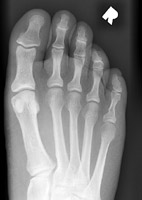

- Click on the image for a larger versionCAP radiograph of the foot shows a small fracture of the fifth proximal phalanx.